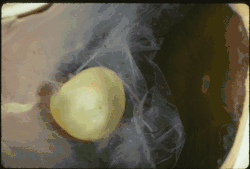

| Ectopia lentis in Marfan syndrome: Zonular fibers are seen. | |

In Marfan syndrome, the health of the eye can be affected in many ways, but the principal change is partial lens dislocation, where the lens is shifted out of its normal position.[18] This occurs because of weakness in the ciliary zonules, the connective tissue strands which suspend the lens within the eye. The mutations responsible for Marfan syndrome weaken the zonules and cause them to stretch. The inferior zonules are most frequently stretched resulting in the lens shifting upwards and outwards, but it can shift in other directions as well. Nearsightedness (myopia), and blurred vision are common due to connective tissue defects in the eye.[19] Farsightedness can also result particularly if the lens is highly subluxated. Subluxation (partial dislocation) of the lens can be detected clinically in about 60% of people with Marfan syndrome by the use of a slit-lamp biomicroscope.[19] If the lens subluxation is subtle, then imaging with high-resolution ultrasound biomicroscopy might be used.[20]